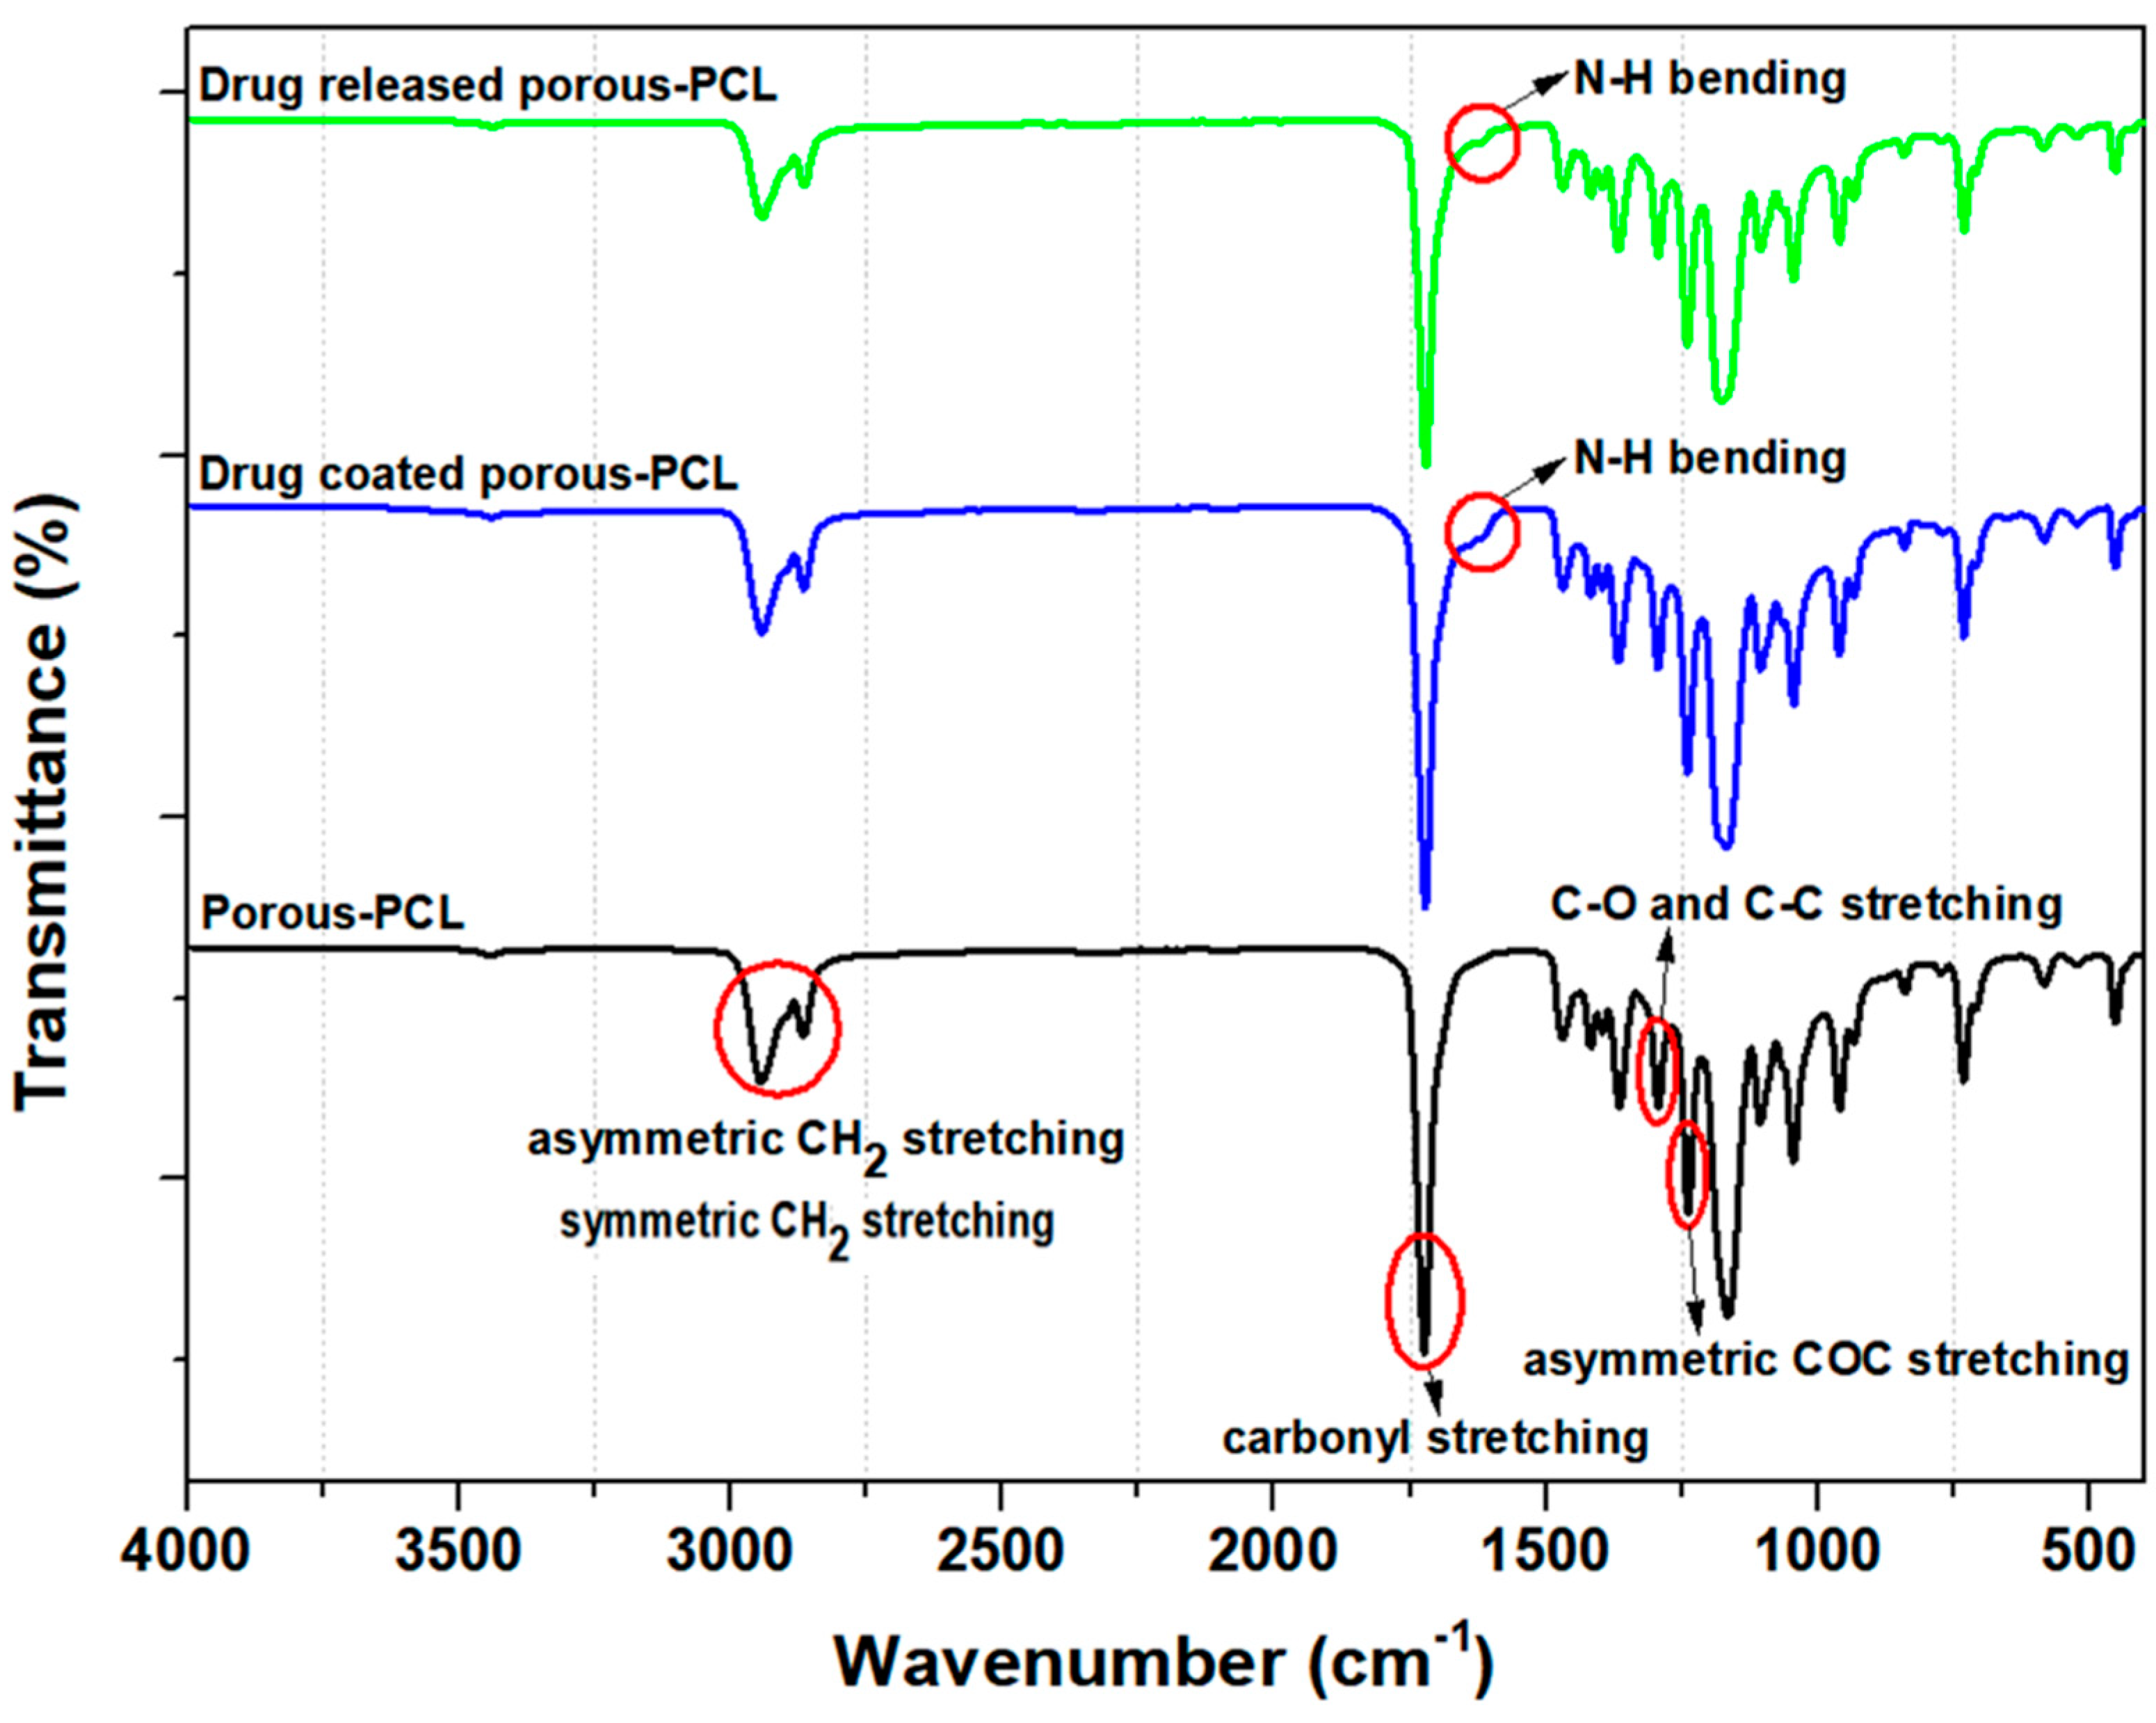

2.5.3. Fourier Transform Infrared Spectroscopy (FT-IR)